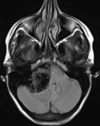

Q

A

Esclerose mesial temporal

Observe a perda de volume, que indica atrofia e causa aumento secundário do corno temporal do ventrículo lateral.

O sinal alto no hipocampo reflete a gliose.